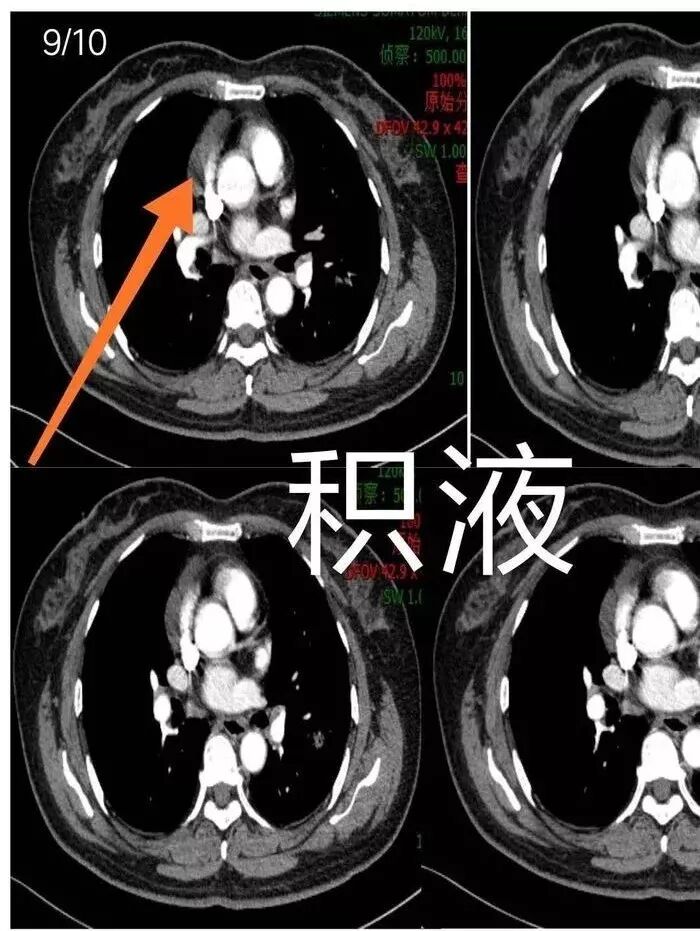

是积液还是囊肿?Coke with ice:我倾向于囊肿初学者:心包隐窝?主要没有连续图

这些好像也大,会不会是肿大淋巴结

看看这个。左边为什么会胸膜往上?因为左边是GGO为主,右边是比较实,就占位效应出来,所以凸出来了心灵鸡汤:@岳微-辽宁省朝阳234医院-影像诊断 应该是心包隐窝初学者:如是炎症,是同步发生,首先边缘不会有边界清楚的GGO,慢性炎症应该连渗出都很少了,更加不会有一部分是收缩,一部分是膨隆